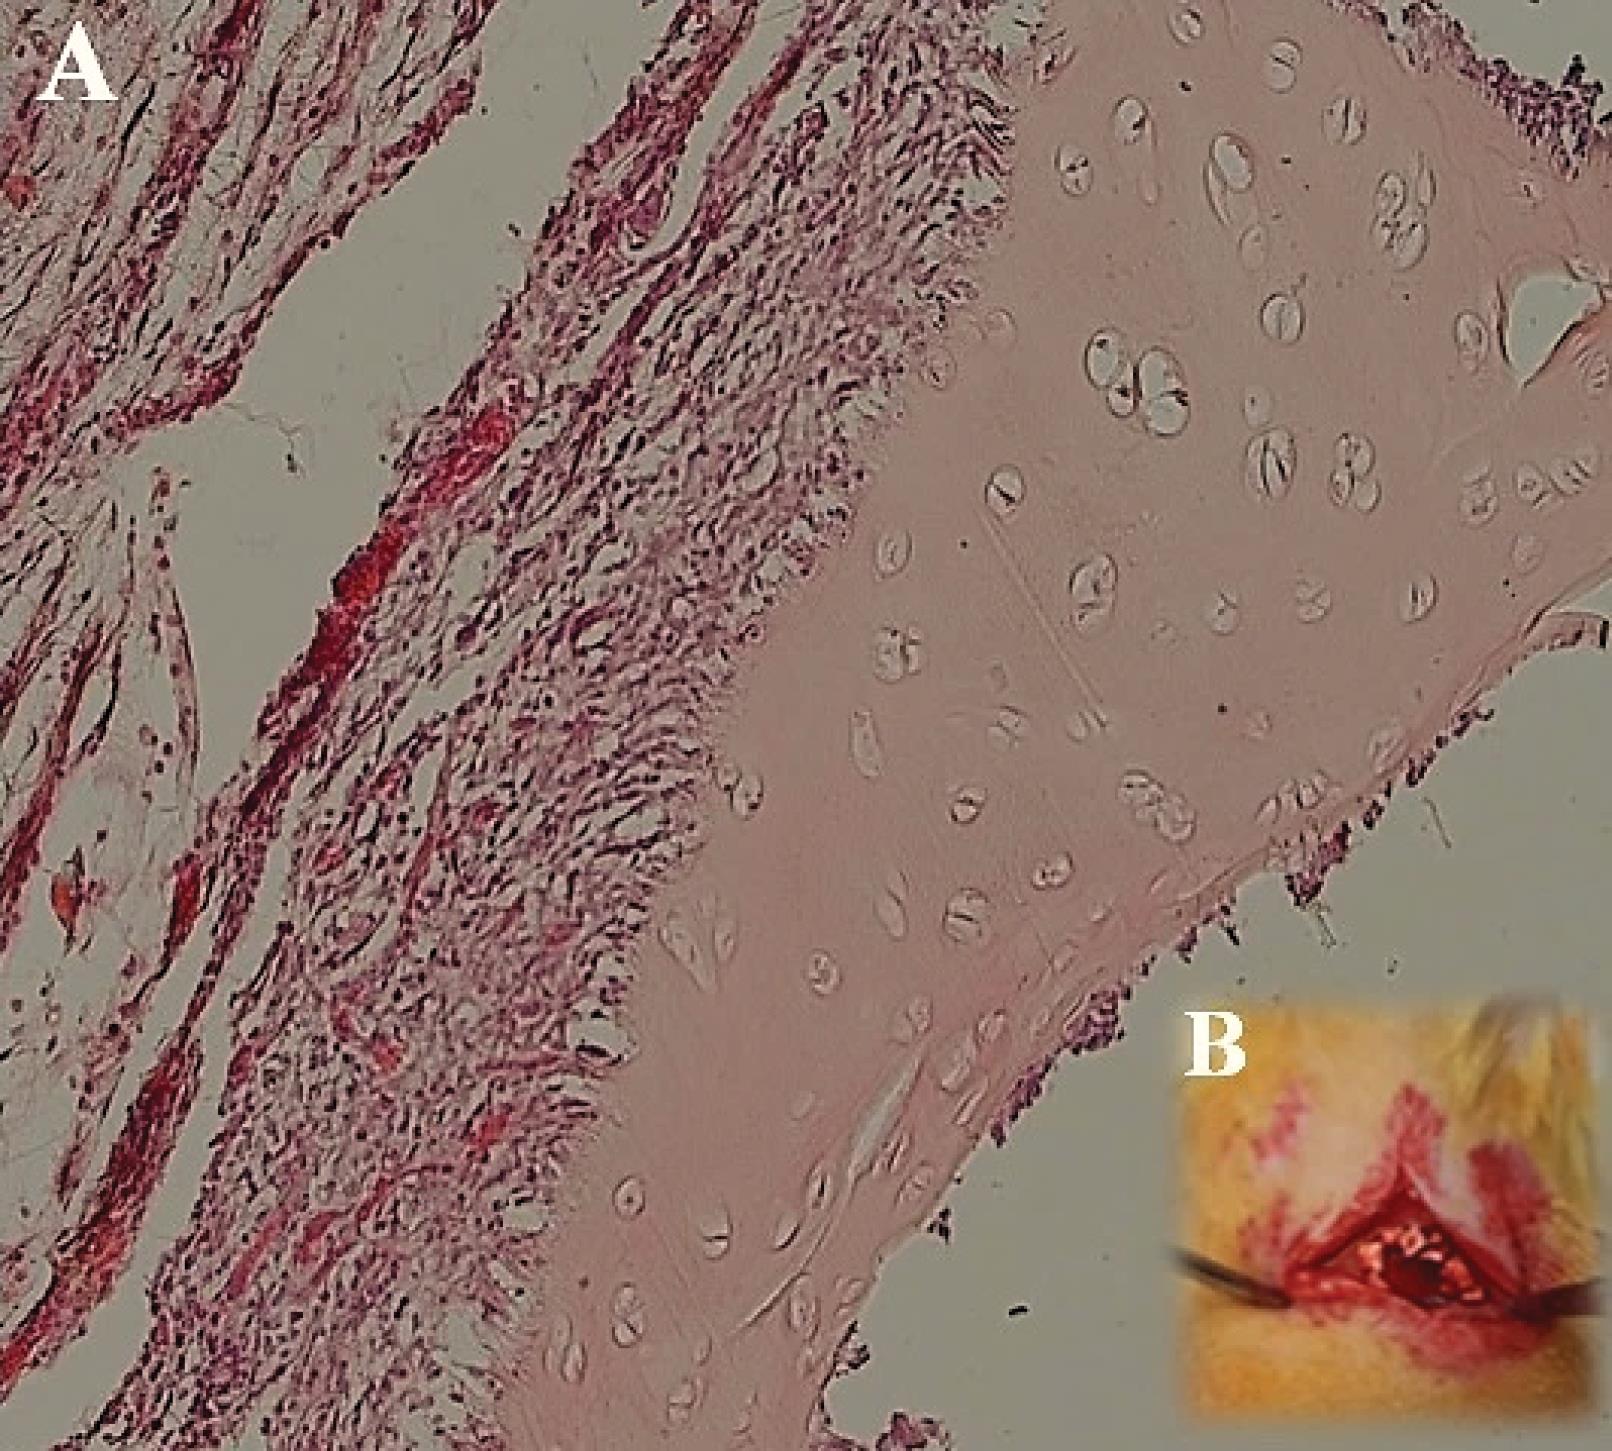

In vivo studies were conducted to assess the biocompatibility and bioactivity of DC cartilage after transplantation. The results indicated that none of the rats died during the transplant experiment, and no significant complications or infections were observed during the 2-week follow-up period after surgery. Macroscopic observations also revealed no signs of graft rejection. However, histological examination using H&E staining revealed the presence of a few number of host cells, such as lymphocytes and fibroblasts. Additionally, a few pieces of cartilage were observed after 2 weeks, which had integrated into the skin of the animal as shown in Fig. 8.

Fig. 8.

After implantation of decellularized (DC) cartilage under the skin of rats, no signs of rejection were observed 2 weeks after surgery. The cartilage had integrated into the skin layer within this time frame. Hematoxylin and Eosin (H&E) staining at 40x magnification showed the presence of host cells, such as lymphocytes and fibroblasts. Fig. A shows the DC cartilage implanted in the skin after 2 weeks, while Fig. B depicts the surgical procedure using DC cartilage under the skin of a rat.